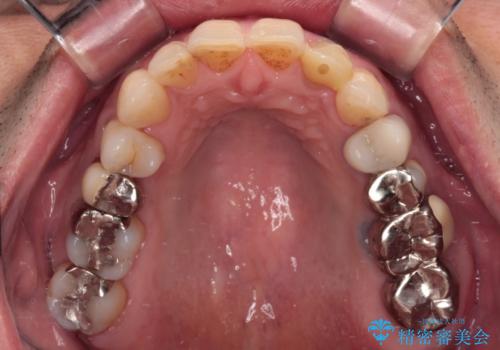

根管治療の土台のまま放置してしまった前歯 オールセラミッククラウンによる補綴治療

土台の状態は良好であったため、仮歯に置き換えた上でオールセラミッククラウンにて補綴治療を行うこととしました。

見た目の改善はもちろんですが、ものが挟まらなくなったり、舌触りが良くなったりと、口腔内の状態が改善されました。